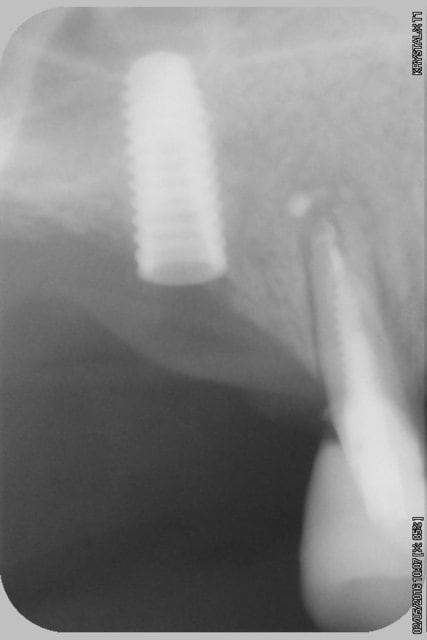

photo 1 ostéotension 2,3, et 4 la suite 21 jours après